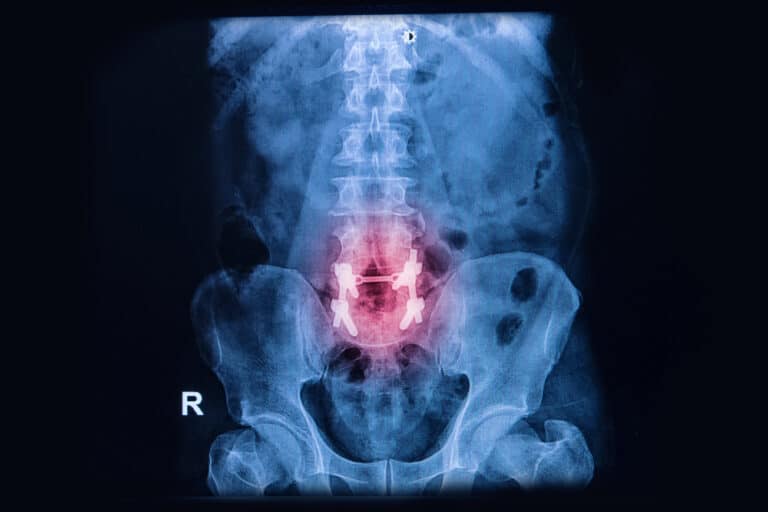

Cauda Equina Syndrome In A Texas Workers’ Compensation Claim Low back injuries are one of the most common types of injuries that people sustain at work. Even so, it is fairly rare to see Read More »